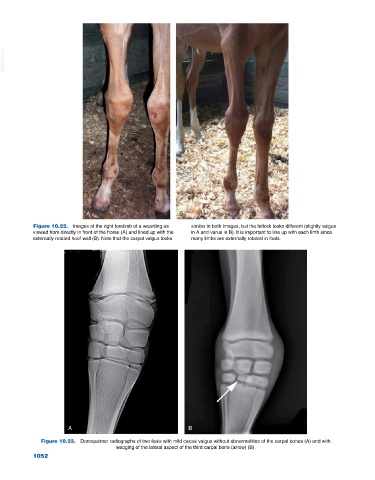

Figure 10.22. Images of the right forelimb of a weanling as similar in both images, but the fetlock looks different (slightly valgus

viewed from directly in front of the horse (A) and lined up with the in A and varus in B). It is important to line up with each limb since

externally rotated hoof wall (B). Note that the carpal valgus looks many limbs are externally rotated in foals.

Figure 10.23. Dorsopalmar radiographs of two foals with mild carpal valgus without abnormalities of the carpal bones (A) and with

wedging of the lateral aspect of the third carpal bone (arrow) (B).